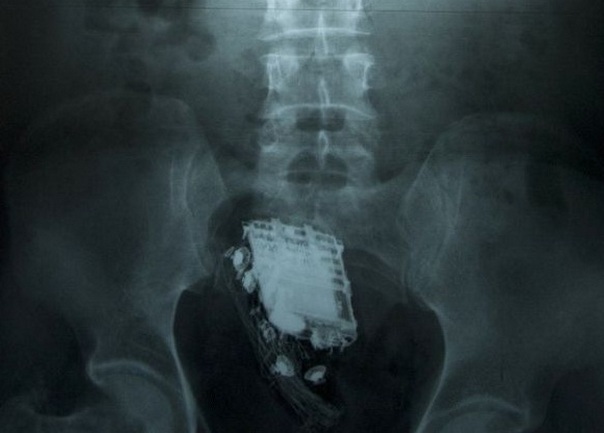

Jedan je zatvornik u šrilankanskom zatvoru za vrijeme pretraživanja ćelije nedozvoljeni mobitel odlučio sakriti - u rektum

mobitel u rektumuNa njegovu veliku žalost, uređaj je ipak otkriven i to zato što čuvari u nekom trenutku začuli kako glazba dopire iz smjera njegove stražnjice, potvrdili su iz lokalne bolnice ovog petka, prenosi AFP.

58-godišnji osuđenik morao je biti prevezen u bolnicu u Colombu kako bi mobitel bio izvađen iz njega: "Muškarac je u u sebe sakrio mobitel. Na njegovu žalost on je zazvonio u najgorem mogućem trenutku i čuvari su shvatili odakle zvuk dolazi", izjavio je neimenovani službenik.

Muškarac je u bolnici proveo dva dana, ali ovog je petka otpušten i vraćen u zatvor: služi 10-godišnju kaznu zbog krađe.